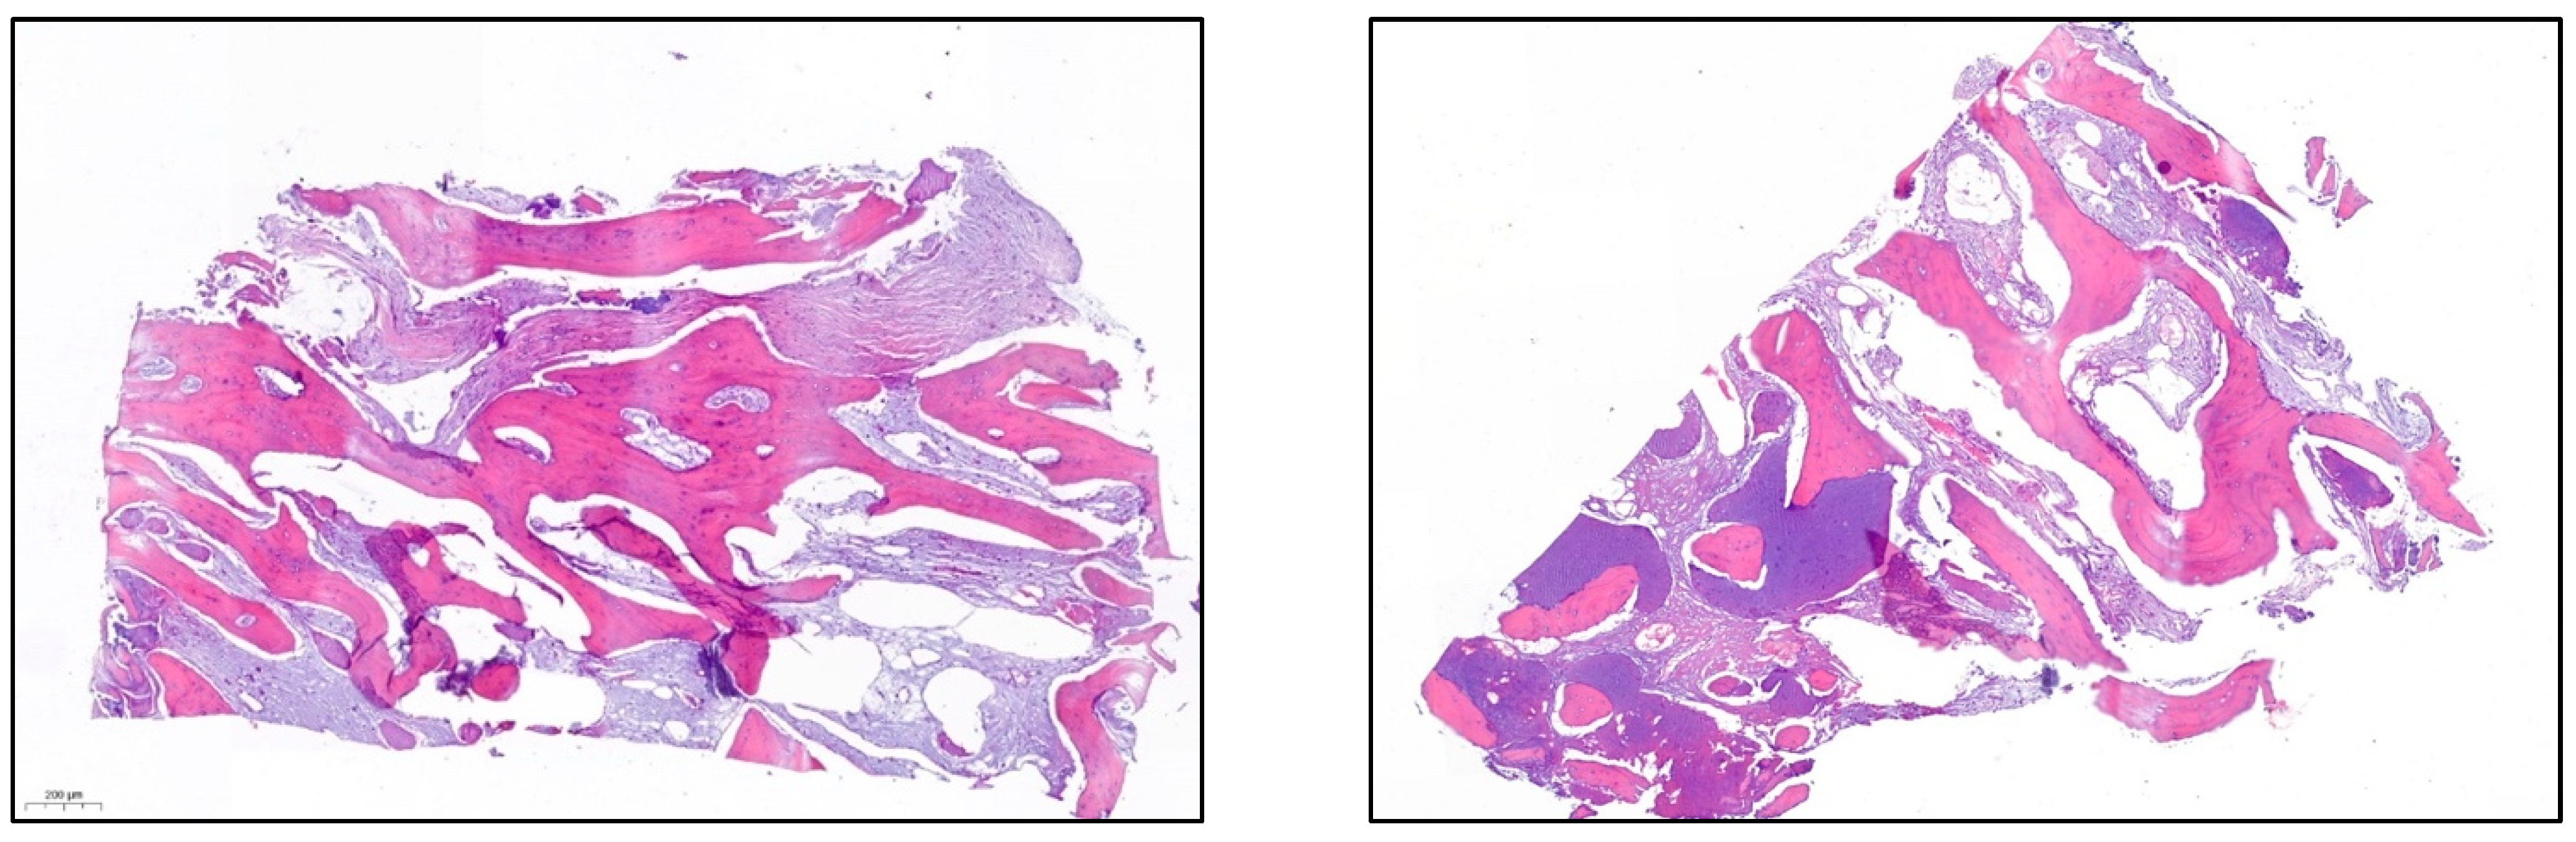

- After 7 and a half months, the Avinent® 3.8 × 8.5 implants were placed in position 3.5 and 4 × 8.5 in position 3.6 (Figure 11). The torque of the implants was greater than 45 N/cm. The ISQ of both implants was taken, being 82 buccal and palatal for the implant in position 3.5 and an ISQ of 57 buccal and palatal for the implant in position 3.6. The bone gain obtained was 1.84 and 1.92 mm in width and 4.2 and 3.78 mm in height for positions 3.5 and 3.6. Simultaneously with the placement of the implants, a bone biopsy was performed between the implants, using a 2 mm bone trephine (Sanhigia, Bujaraloz, Spain) (Figure 12). Three months after the placement of the implants, the implants were rehabilitated using metal-ceramic screw-retained crowns.